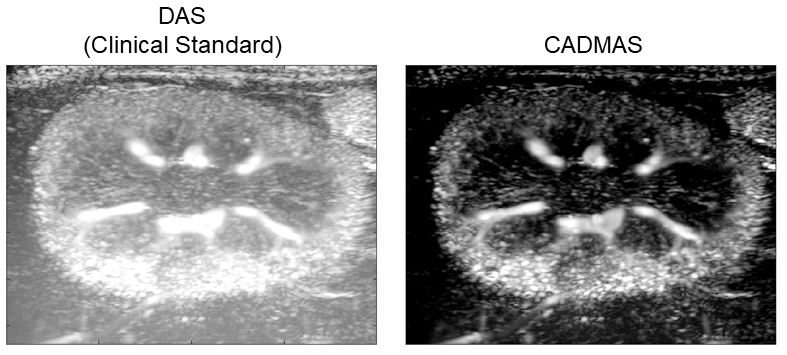

We present an enhanced nonlinear beamforming algorithm, which takes advantage of the coherence of received signals across elements and angles called Cross-Angular Delay Multiply and Sum Beamforming (CADMAS). This algorithm is capable of producing ultrasound images with improved contrast, noise suppression, and resolution, all at a negligible computational cost.